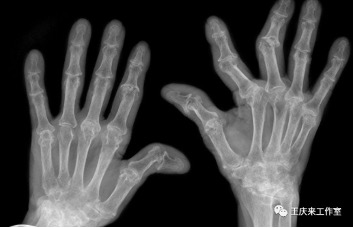

04辅助检查

类风湿关节炎患者类风湿因子阳性率达75%,骨关节炎患者的类风湿因子呈阴性。

另外抗环瓜氨酸抗体检测也有助于类风湿性关节炎的诊断。也可以根据关节B超、放射线检查等对诊断做出帮助。